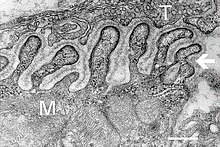

Die neuromuskuläre synaptische Verknüpfung besteht aus dem präsynaptischen Anteil des Axolemms einer Nervenzelle und dem postsynaptischen Anteil des Sarkolemms einer Muskelzelle, getrennt durch einen synaptischen Spalt mit feinfaseriger Basallamina. Bei Erregung der Nervenzelle setzt die präsynaptische Endigung des Axons den Botenstoff Acetylcholin (ACh) frei, der sich im synaptischen Spalt verteilt und spezifische Rezeptormoleküle (ACh-Rezeptoren) in der postsynaptischen Membranregion einer Muskelfaser erreicht. Deren Oberfläche ist hier durch eine Vielzahl von Einfaltungen vergrößert (subneuraler Faltenapparat).